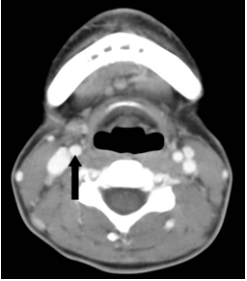

46 附圖中黑色箭號所指的構造為何?

(A)上腔靜脈 (B)右側頸動脈 (C)左側內頸靜脈 (D)右側內頸靜脈